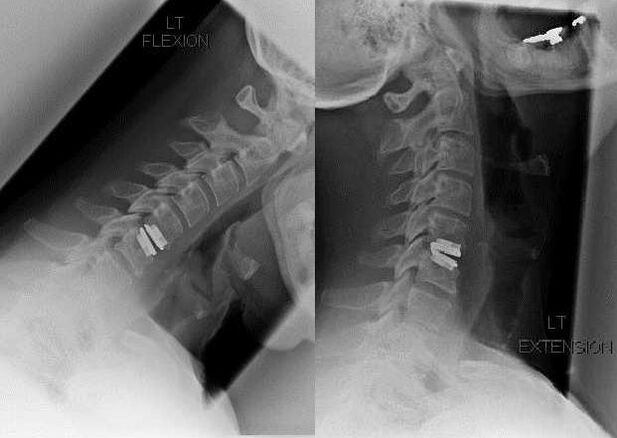

Surgical intervention

Indications for surgical intervention, inefficiency of conservative treatment, as well as complications of cervical osteochondrosis, for example, myelopathy, vertebral artery syndrome and radicular syndrome.To decompress the spinal cord, blood vessels and spinal roots, the following operations:

- Laminectomy;

- Laminotomy;

- foraminotomy;

- Facetectomy;

- discectomy.

During surgery, bone fragments and ligaments can be resected, and intervertebral discs can be removed in whole or in part.For small herniated disc protrusions, laser ablation of the disc nucleus is often performed.

After extensibility of the lamellar structures, stabilization of the spinal motion segments is often required, with spinal fusion or placement of bone and dermal autografts.